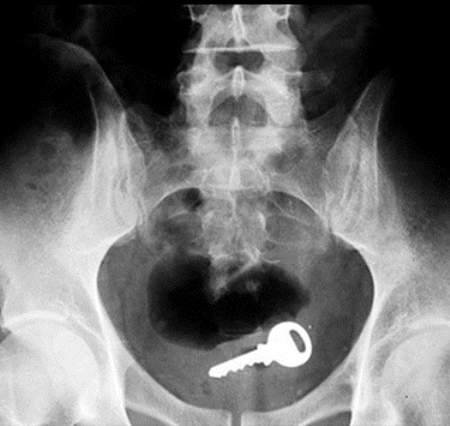

What Got Stuck In Our Genitals This Year?

US Consumer Product Safety Commission Reveals What Went Up Our Butts!

According too Adequate Man, The US Consumer Product Safety Commission released a list of objects that had to be removed from someone’s body during emergency room visits in 2017. Talk about facepalm! What were some people thinking? While the list goes through specific body parts, obviously the most fun to know are what, literally, was up your butt this year. Check out the lists below!